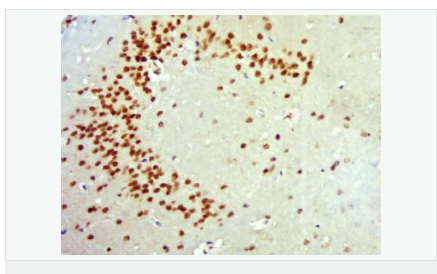

細(xì)胞定位細(xì)胞核 分泌型蛋白

產(chǎn)品介紹Neurotrophins function to regulate naturally occurring cell death of neurons during development. The prototype neurotrophin is nerve growth factor (NGF), originally discovered in the 1950s as a soluble peptide promoting the survival of, and neurite outgrowth from, sympathetic ganglia. More recently, three additional structurally homologous neurotrophic factors have been identified. These include brain-derived neurotrophic factor (BDNF), neurotrophin-3 (NT-3) and neurotrophin-4 (NT-4), also designated NT-5. These various neurotrophins stimulate the in vitro survival of distinct but partially overlapping populations of neurons. The Trk A receptor is the preferential receptor for NGF, but also binds NT-3 and NT-4. The Trk B receptor binds equally well to both BDNF and NT-4 and to a lesser extent NT-3, while the Trk C receptor only binds NT-3. BDNF promotes the survival of neuronal populations that are all located either in the central nervous system or directly connected to it. Belongs to the NGF-beta family.

During development, promotes the survival and differentiation of selected neuronal populations of the peripheral and central nervous systems. Participates in axonal growth, pathfinding and in the modulation of dendritic growth and morphology. Major regulator of synaptic transmission and plasticity at adult synapses in many regions of the CNS. The versatility of BDNF is emphasized by its contribution to a range of adaptive neuronal responses including long-term potentiation (LTP), long-term depression (LTD), certain forms of short-term synaptic plasticity, as well as homeostatic regulation of intrinsic neuronal excitability.

Tissue Specificity:

Brain. Highly expressed in hippocampus, amygdala, cerebral cortex and cerebellum. Also expressed in heart, lung, skeletal muscle, testis, prostate and placenta.